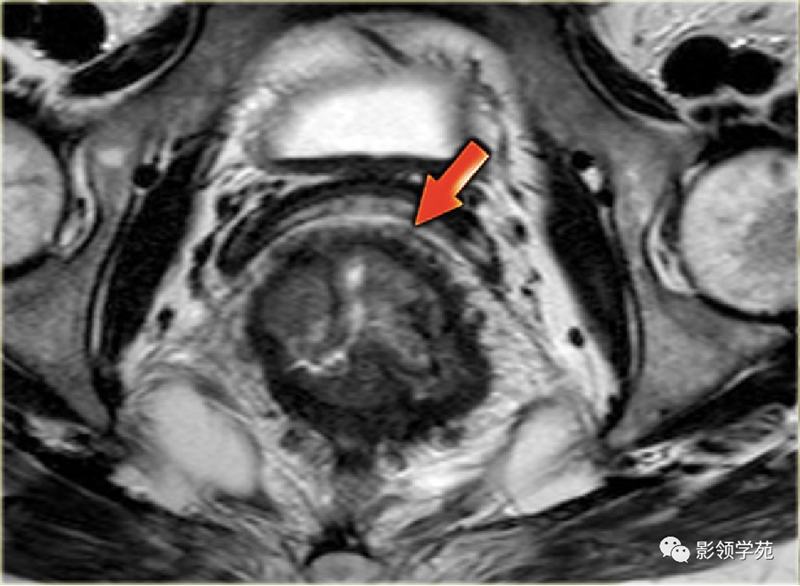

1、影像学检查:如X线胃肠道钡餐造影、CT检查、MRI检查、经直肠超声检查。腹部X线检查适用于伴发急性肠梗阻病人,可见梗阻部位上方的结肠有充气胀大现象。直肠癌术前行直肠MRI为常规检查项目,是术前分期的重要依据。

直肠癌磁共振影像